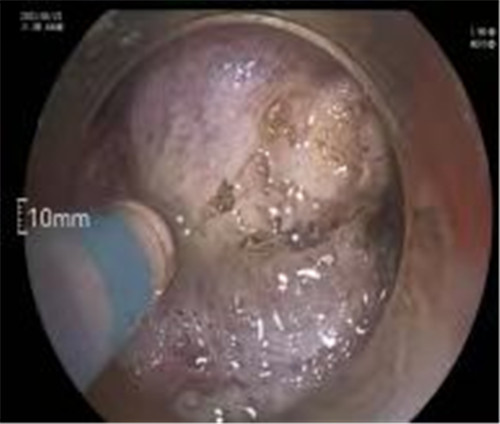

通過(guò)內(nèi)鏡切開(kāi)瘤體表面粘膜,分離后挖除瘤體,或以消化道全層切除的方法切除瘤體,并在內(nèi)鏡下縫合切口。與傳統(tǒng)手術(shù)相比,該項(xiàng)技術(shù)利用了人體自然通道,不會(huì)破壞人體結(jié)構(gòu),更加微創(chuàng)。不超過(guò)3cm向消化道腔內(nèi)生長(zhǎng)為主的良性或低度惡性粘膜下腫瘤(如間質(zhì)瘤、類癌、平滑肌瘤等),都可采用ESE治療。

近期病例之一,圖片依次為:胃鏡、超聲胃鏡、ESE術(shù)中、術(shù)后、切下病變。